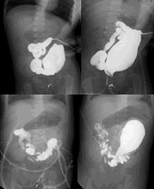

(2)短结肠末端分离(无瘘者)或结扎(有瘘者)后结肠造瘘术该术式可避免尿路感染但有一定难度因短结肠高度扩张减压后才能处理末端造瘘方法为短结肠末端造瘘或开窗术。

(3)袋状结肠部分切除整形(使袋状结肠管状化保留直径15~20mm)后造瘘术该法能最大限度保留结肠但有时保留的结肠无蠕动功能。

(1)袋状结肠切除回肠或结肠拖出型肛门成形术。

(2)袋状结肠部分切除整形后拖出型肛门成形术。